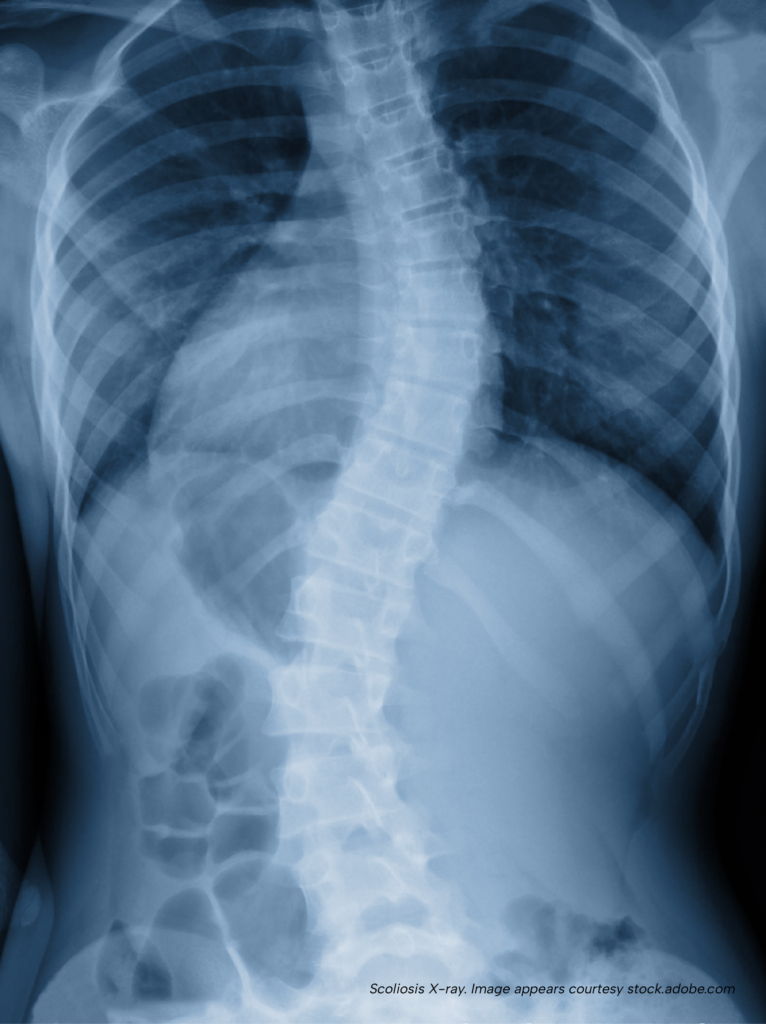

Mild scoliosis is somewhat common in CMT. Scoliosis is a sideways curvature of the spine, and in some cases it can become severe enough to reduce the size and shape of the chest cavity. When the chest cavity becomes smaller, it cannot expand as well. This limits how much the lungs can inflate, which reduces total lung capacity. Over time, this can decrease lung distensibility (the lungs ability to stretch as they fill) and eventually create a true restriction to airflow into the lungs. When scoliosis in CMT becomes severe enough to impact breathing, it is called CMT-induced scoliosis-related restrictive lung disease.

CMT-related scoliosis can be challenging, but it is rare for it to become severe enough to affect lung function. When it does, corrective spine surgery is usually recommended. Although CMT itself does not cause restrictive lung disease, a severe scoliosis caused by CMT can lead to restrictive lung disease if the curvature becomes severe enough to interfere with breathing.